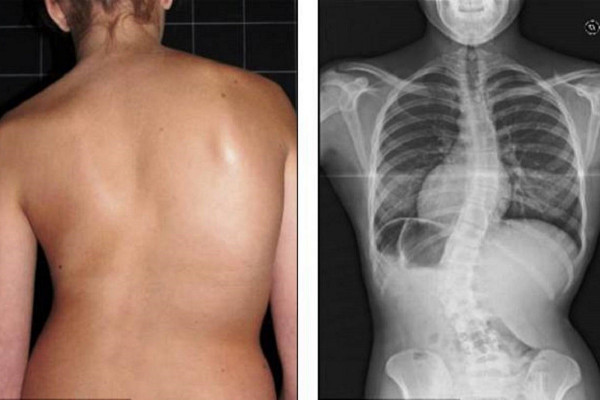

Заболевания опорно-двигательного аппарата

Опорно-двигательный аппарат человека – это комплекс из костей скелета, мышечных тканей и связующего дополнения (сухожилий и связок). Это основа организма, дающая человеку возможность передвигаться, сидеть, принимать различные позы. Поэтому травмы и заболевания опорно-двигательного аппарата становятся причиной сильного ухудшения качества жизни человека. В тяжелых случаях может наступить полная потеря двигательной функции.

7. Ношение неудобной обуви на высоком каблуке. Такая обувь, особенно в юном возрасте, приводит к сколиозу.